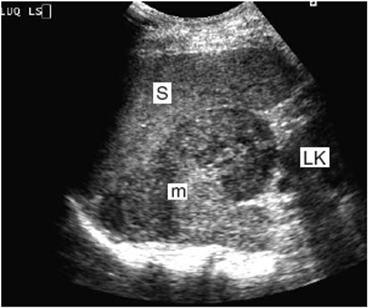

Metastatic Disease To The pancreas And Spleen

Metastatic Disease to the Pancreas and Spleen Shayna L. Showalter, Eric Hager, and Charles J. Yeo Isolated metastases to the pancreas and spleen are a rare occurrence. ... Read More